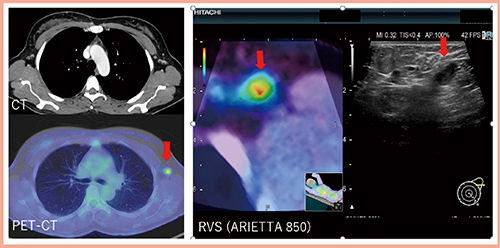

また,RVSはPET/CTとの同期も可能である。症例2(図3)は,右腋窩にPETにてリンパ節への集積(↓)を認めた。CTでは皮質の肥厚を認めず,初回超音波では病変は不明確であったが,RVSによるSecond-look USを施行したところ,正常なリンパ皮質の部分的な肥厚が確認できた(図3右)。穿刺吸引細胞診の結果は陽性であった。

図3 症例2(38歳):PETにて右腋窩にリンパ節への集積を認めた症例